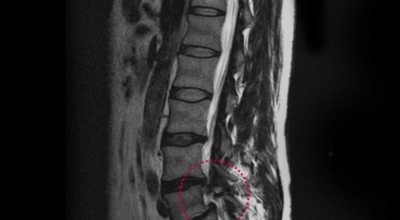

디스크는 그 특수한 구조 때문에 웬만한 힘이 가해져도 효율적으로 쿠션 역할을 할 수 있겠습니다. 그러나 갑작스럽게 무거운 물건을 들어 올리거나, 부자연스러운 자세를 장시간 취하면 디스크에 무리한 힘이 가해지면서 디스크가 밖으로 돌출이 되게 돼요. 심한 경우 디스크를 감싼 막이 터지면서 그 안에 있는 수핵이 튀어나오게 돼요. 디스크는 대부분이 후방이나 후외방으로 돌출되는데 이 경우에 바로 곁에 있는 신경을 누르게 된다고 해요.

돌출된 디스크는 척추의 어느 부위에나 발생할 수 있답니다. 목에 생기면 '목 디스크', 등에 생기면 '등 디스크', 허리에 생기면 '허리 디스크'라고 부른다고 해요. 이와 같이 디스크가 돌출되어 신경을 눌러 요통 및 다리가 아프고 저린 증상을 일으키는 병을 '추간판 탈출증' 또는 '디스크 탈출증'이라고도 불리워요. 발생 빈도별로 보면 허리 디스크가 가장 흔해요. 그다음이 목 디스크입니다. 등 디스크는 드문 병이라고 하네요.